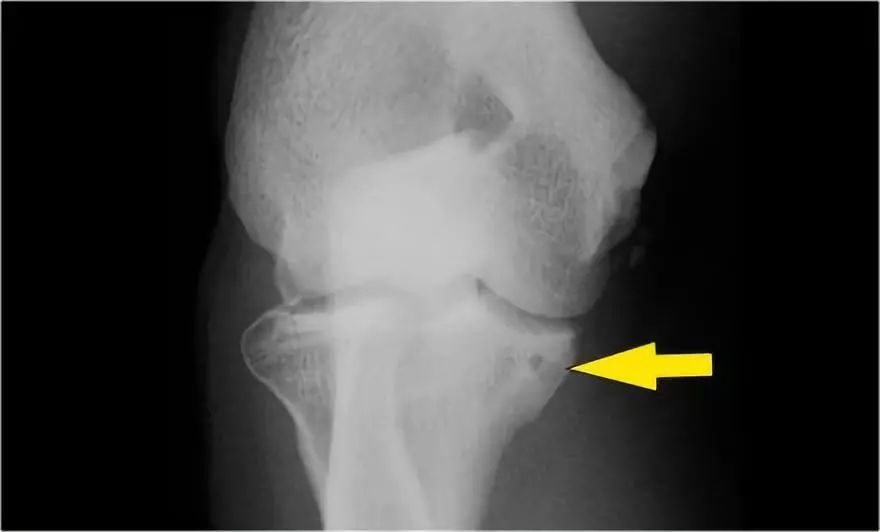

肘关节脱位这是一个患者肘部的侧位片。X光片显示关节积液(红色箭头)和冠状突骨折(黄色箭头)。

下面是MR● 冠状图片:侧副韧带完全剥离(黄色箭头)。桡骨头是半脱位的。由于骨折引起的冠突骨髓水肿(红色箭头)。● 矢状面观:桡骨头稍后有点半脱位(黄色箭头)。大量积液和囊后破裂。● 由于冠状突的撞击(红色箭头)导致的头颅后侧的挫伤。所有这些迹象都是后脱位的结果。